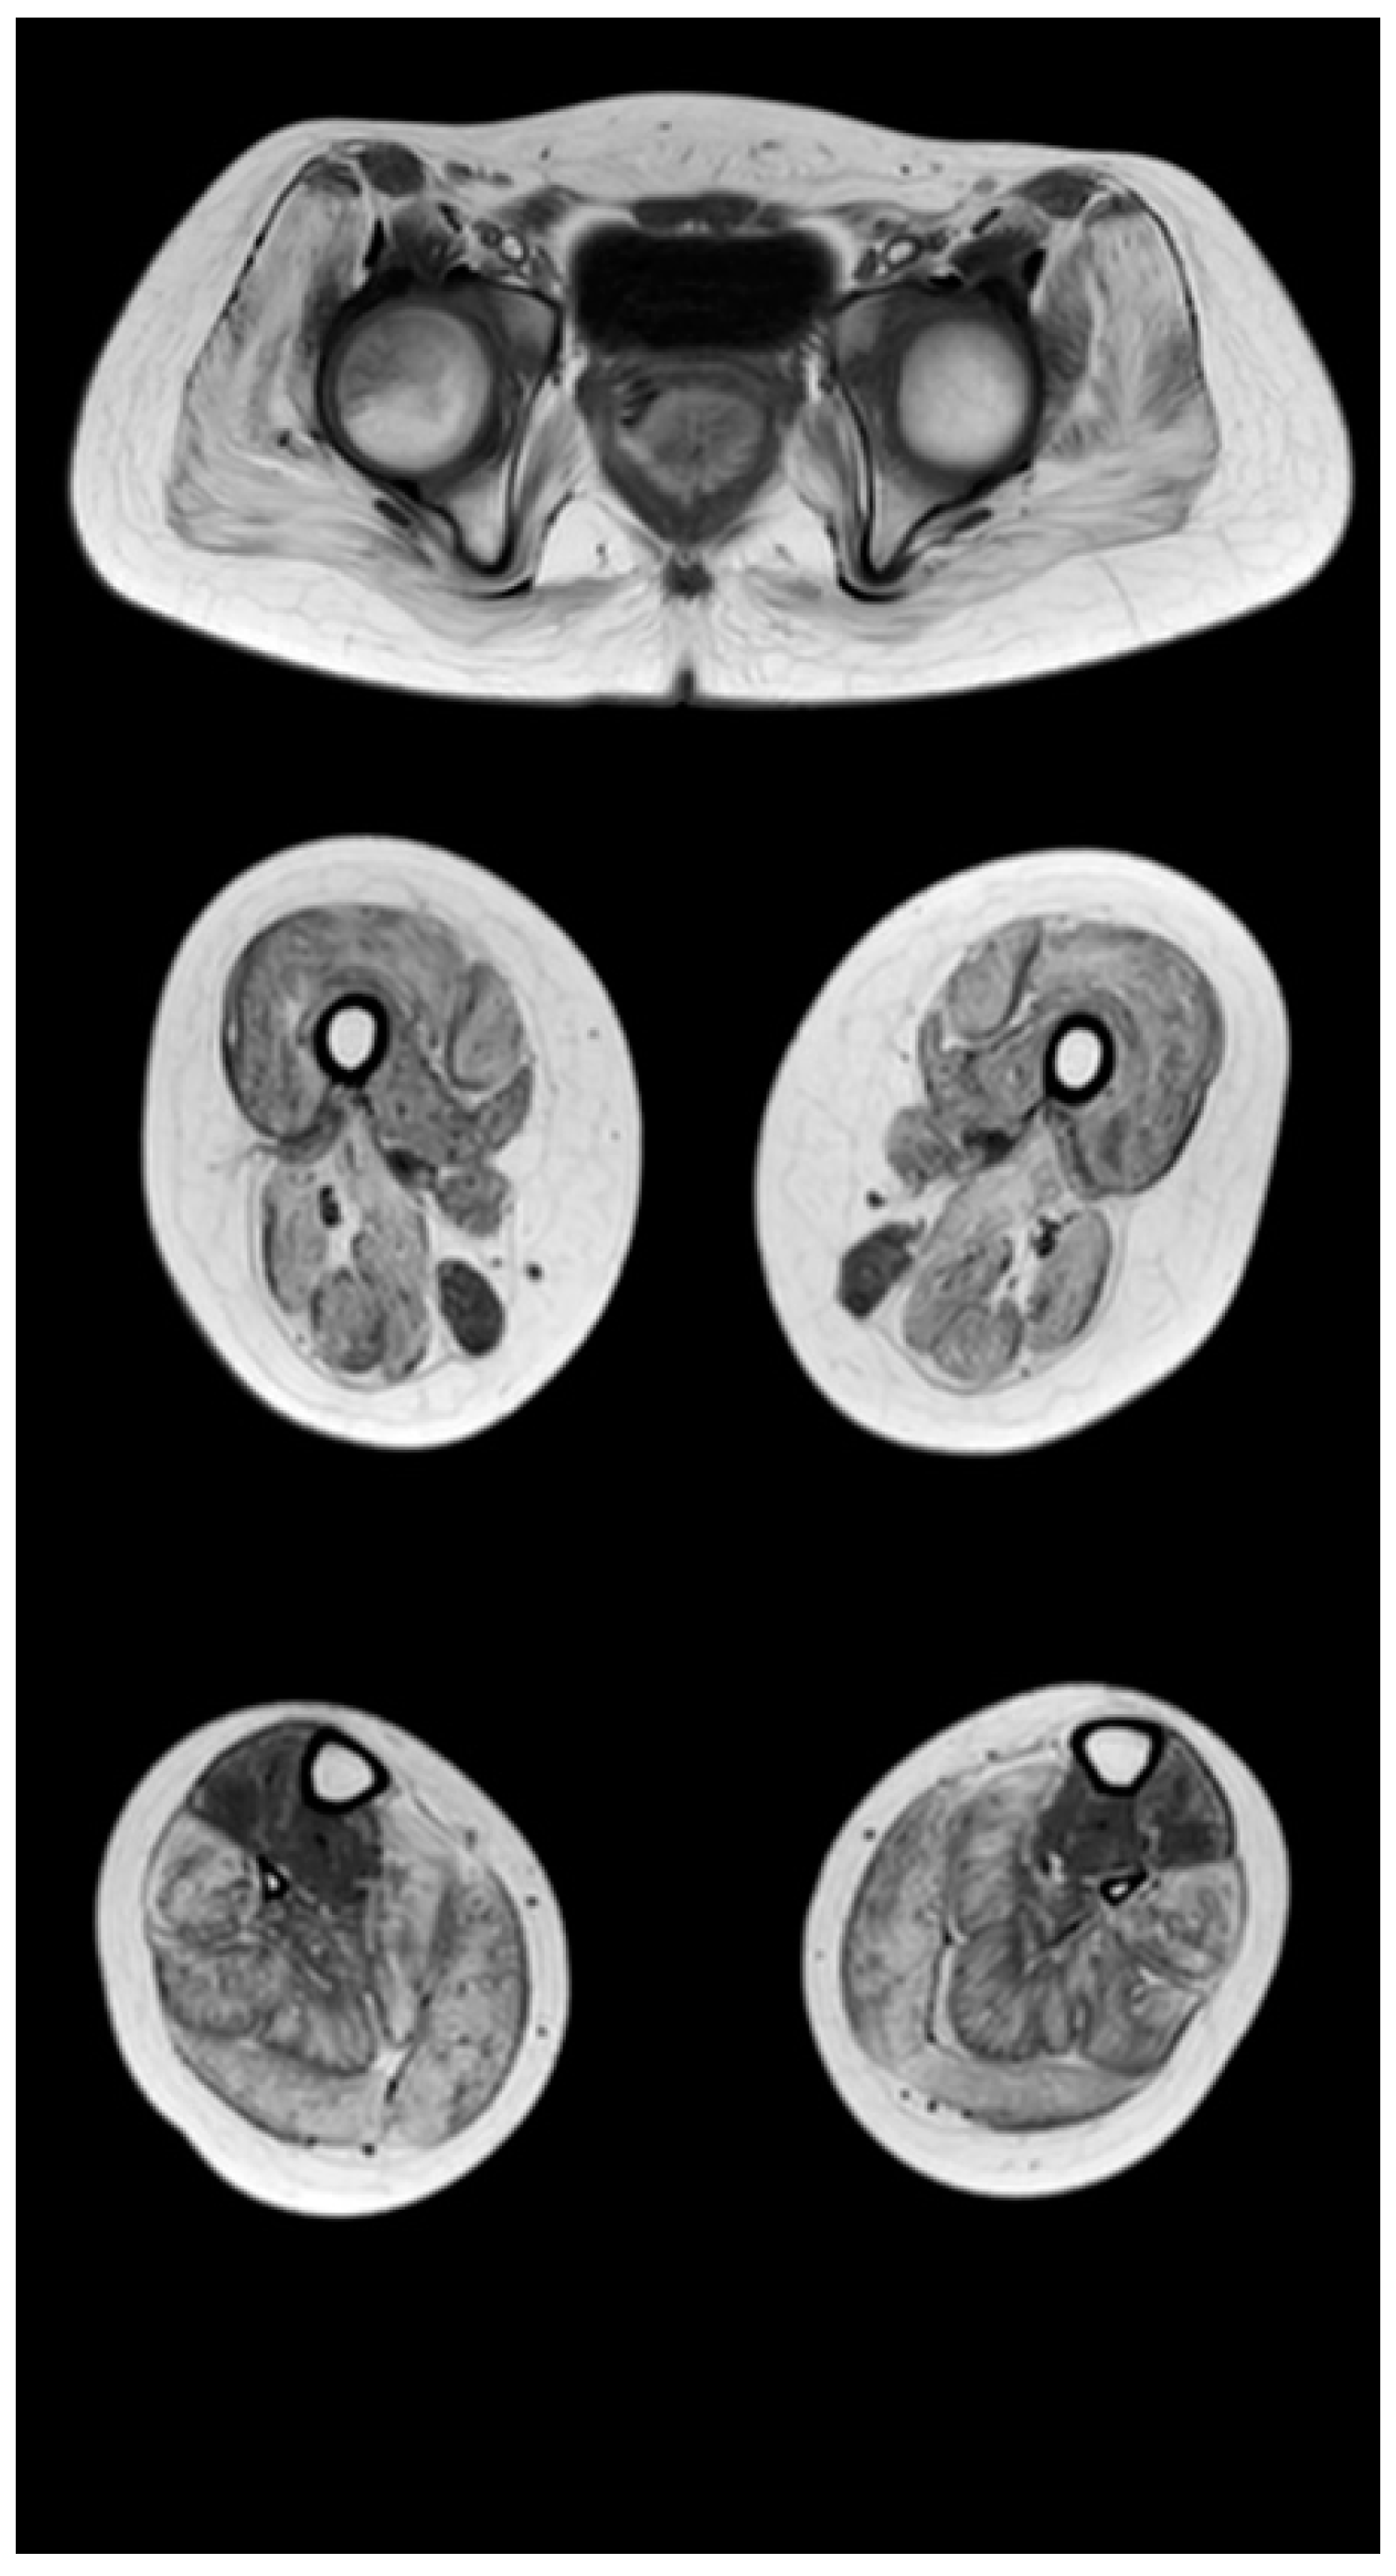

Figure 5.

Pattern of involvement of the muscles of the lower extremities in a patient at a late non-ambulatory stage of the disease (13 years). From top to bottom: the pelvic level, the femoral level, and the level of the legs.

Figure 5 shows the pattern of lower limb muscle involvement in a patient in the late non-ambulatory stage of the disease. The late non-ambulatory stage is characterized by total fibro-fatty degeneration of the muscles of the pelvic girdle, hips, and legs (stage 4). Noteworthy is the negative pattern—complete preservation of the gracilis muscle (stage 0) and the anterior muscle group of the legs—of the anterior and posterior tibial muscles (stages 2a and 1, respectively).